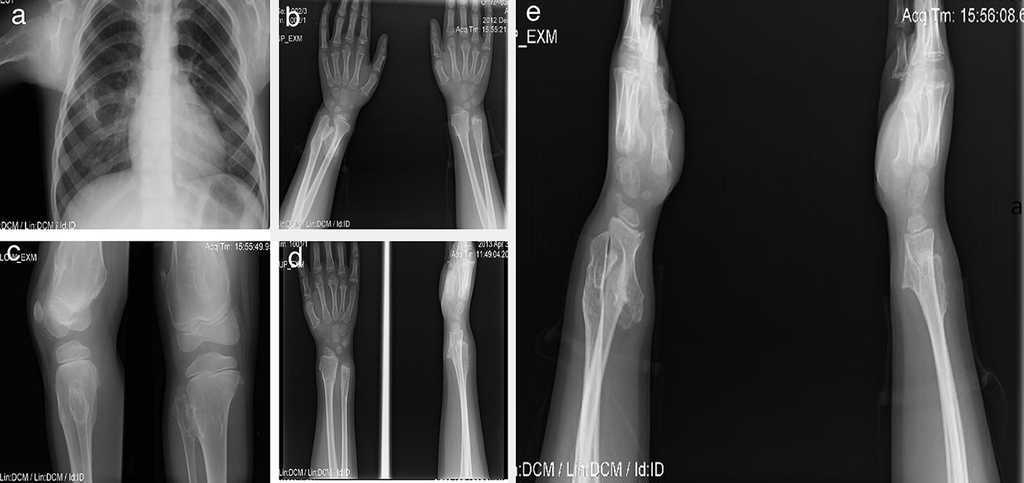

Paciente de sexo masculino de 12 años con antecedentes de hipotiroidismo subclínico que no requirió tratamiento en el primer año de vida. Los osteocondromas se manifestaron desde los 2 años como una deformidad en el tobillo sin fracturas. Posteriormente han aparecido nuevas lesiones en hombro, tibia, muñeca y fémur. Presentó limitaciones en el arco de movimiento articular en muñeca y hombro y dolor ocasional en la movilización de las mismas articulaciones. Su crecimiento ha sido satisfactorio, con estatura en el P50 y sin acortamiento de miembros inferiores (Fig. 3).

Figura 3 Caso 2 (III1). Paciente masculino de 12 años con exostosis en cuello y tercio proximal de húmero, quinto arco costal anterior derecho (a), en región anterolateral de ambos cúbitos, lo que sugiere una deformidad tipo III de la clasificación de Masada (b), tercio distal de fémur con ensanchamiento metadiafisiario (c), y protuberancias en región anterolateral de tibia y cúbito derechos, las cuales aumentaron de tamaño al año siguiente con mayor volumen de las lesiones de ambos cúbitos, principalmente el derecho (d, e).